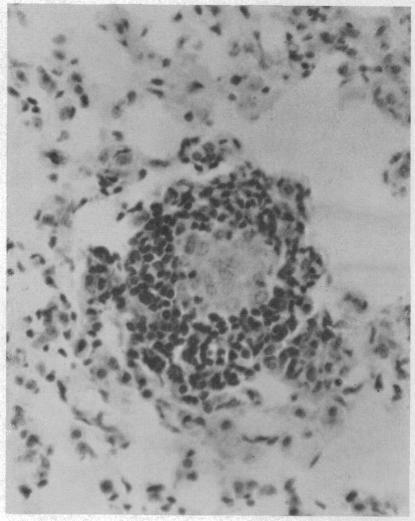

Intravenous vaccination of mice with oil-treated mycobacterial cell walls resulted in a marked macrophage accumulation in the lungs and spleens of vaccinated animals. Injection of oil emulsion alone or of cell walls alone failed to elicit the macrophage response. Although a correlation existed between the magnitude of the macrophage response and the degree of immunity against aerosol challenge with H(37)Rv organisms, the findings presented here do not rule out the possibility that qualitative differences may be present in the macrophages of animals vaccinated against tuberculosis. The ability of oil-treated cell walls to elicit an immune response appeared to be a function of the physical association of cell wall fragments and the surface of oil droplets.

用经油处理的分枝杆菌细胞壁对小鼠进行静脉接种,导致接种动物的肺和脾中出现明显的巨噬细胞聚集。单独注射油乳剂或单独注射细胞壁均未能引发巨噬细胞反应。尽管巨噬细胞反应的强度与针对H(37)Rv菌株气溶胶攻击的免疫程度之间存在相关性,但此处呈现的研究结果并未排除接种抗结核疫苗的动物巨噬细胞中可能存在质量差异的可能性。经油处理的细胞壁引发免疫反应的能力似乎是细胞壁碎片与油滴表面物理结合的一种功能。